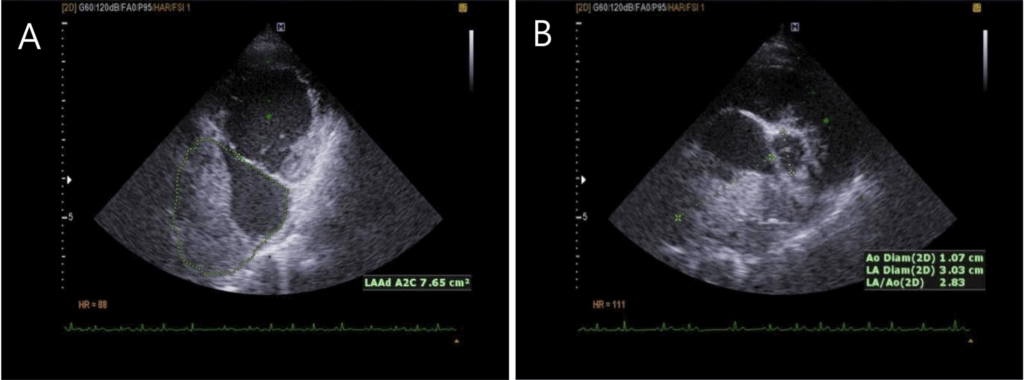

Fig 2. 증례 1에서 얻은 심장초음파 영상입니다. 우측 흉골 옆 단축면(대동맥 수준; A)과 장축 5챔버 영상(B)에서 상행 대동맥, 폐동맥, 좌심방 사이에 14–16mm 크기의 종괴가 관찰되었습니다.

(Echocardiogram images obtained from the case 1. The right parasternal short axis (aortic level; A) and long axis (5 chamber B) of 2 D echocardiography showed 14-16 mm mass grown among ascending aorta, pulmonary artery and left atrium. )

심장초음파 검사 결과

• 심장초음파 검사에서 상행 대동맥과 폐동맥 사이에 약 1.5cm 크기의 종괴가 확인되었습니다.

• 이 종괴로 인해 대동맥 역류, 이첨판 역류, 좌심실 확장이 동반되어 있었으며, 종괴의 위치와 형태를 고려할 때, 대동맥 소체 종양(aortic body tumor)이 의심되었습니다.

• 본 증례의 환자는 심부전 약물 치료와 경구 항암제 투여를 병행하였으며, 6주 추적 검사에서 종괴 크기의 급격한 증가는 보이지 않았고 임상 증상도 안정적으로 유지되었습니다.

심장초음파 결과

• 심장초음파에서 좌심방의 약 60% 이상을 차지하는 종괴가 확인되었습니다.

• 이로 인해 심한 이첨판 역류, 좌심방 확장, 혈류 흐름의 제한이 관찰되었습니다.

• 종괴의 모양과 위치를 바탕으로 심장 점액종(myxoma)이 의심되었습니다.

• 본 증례의 환자는 심장 부담을 줄이기 위한 약물, 혈전 예방 치료, 기관지 확장제를 투여하며 관리하였고, 3개월 추적 검사에서도 종괴 크기의 뚜렷한 증가는 보이지 않았습니다.